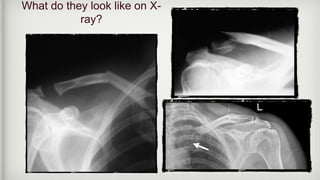

What do they look like on X-

ray?

What do theylook like on X- ray?